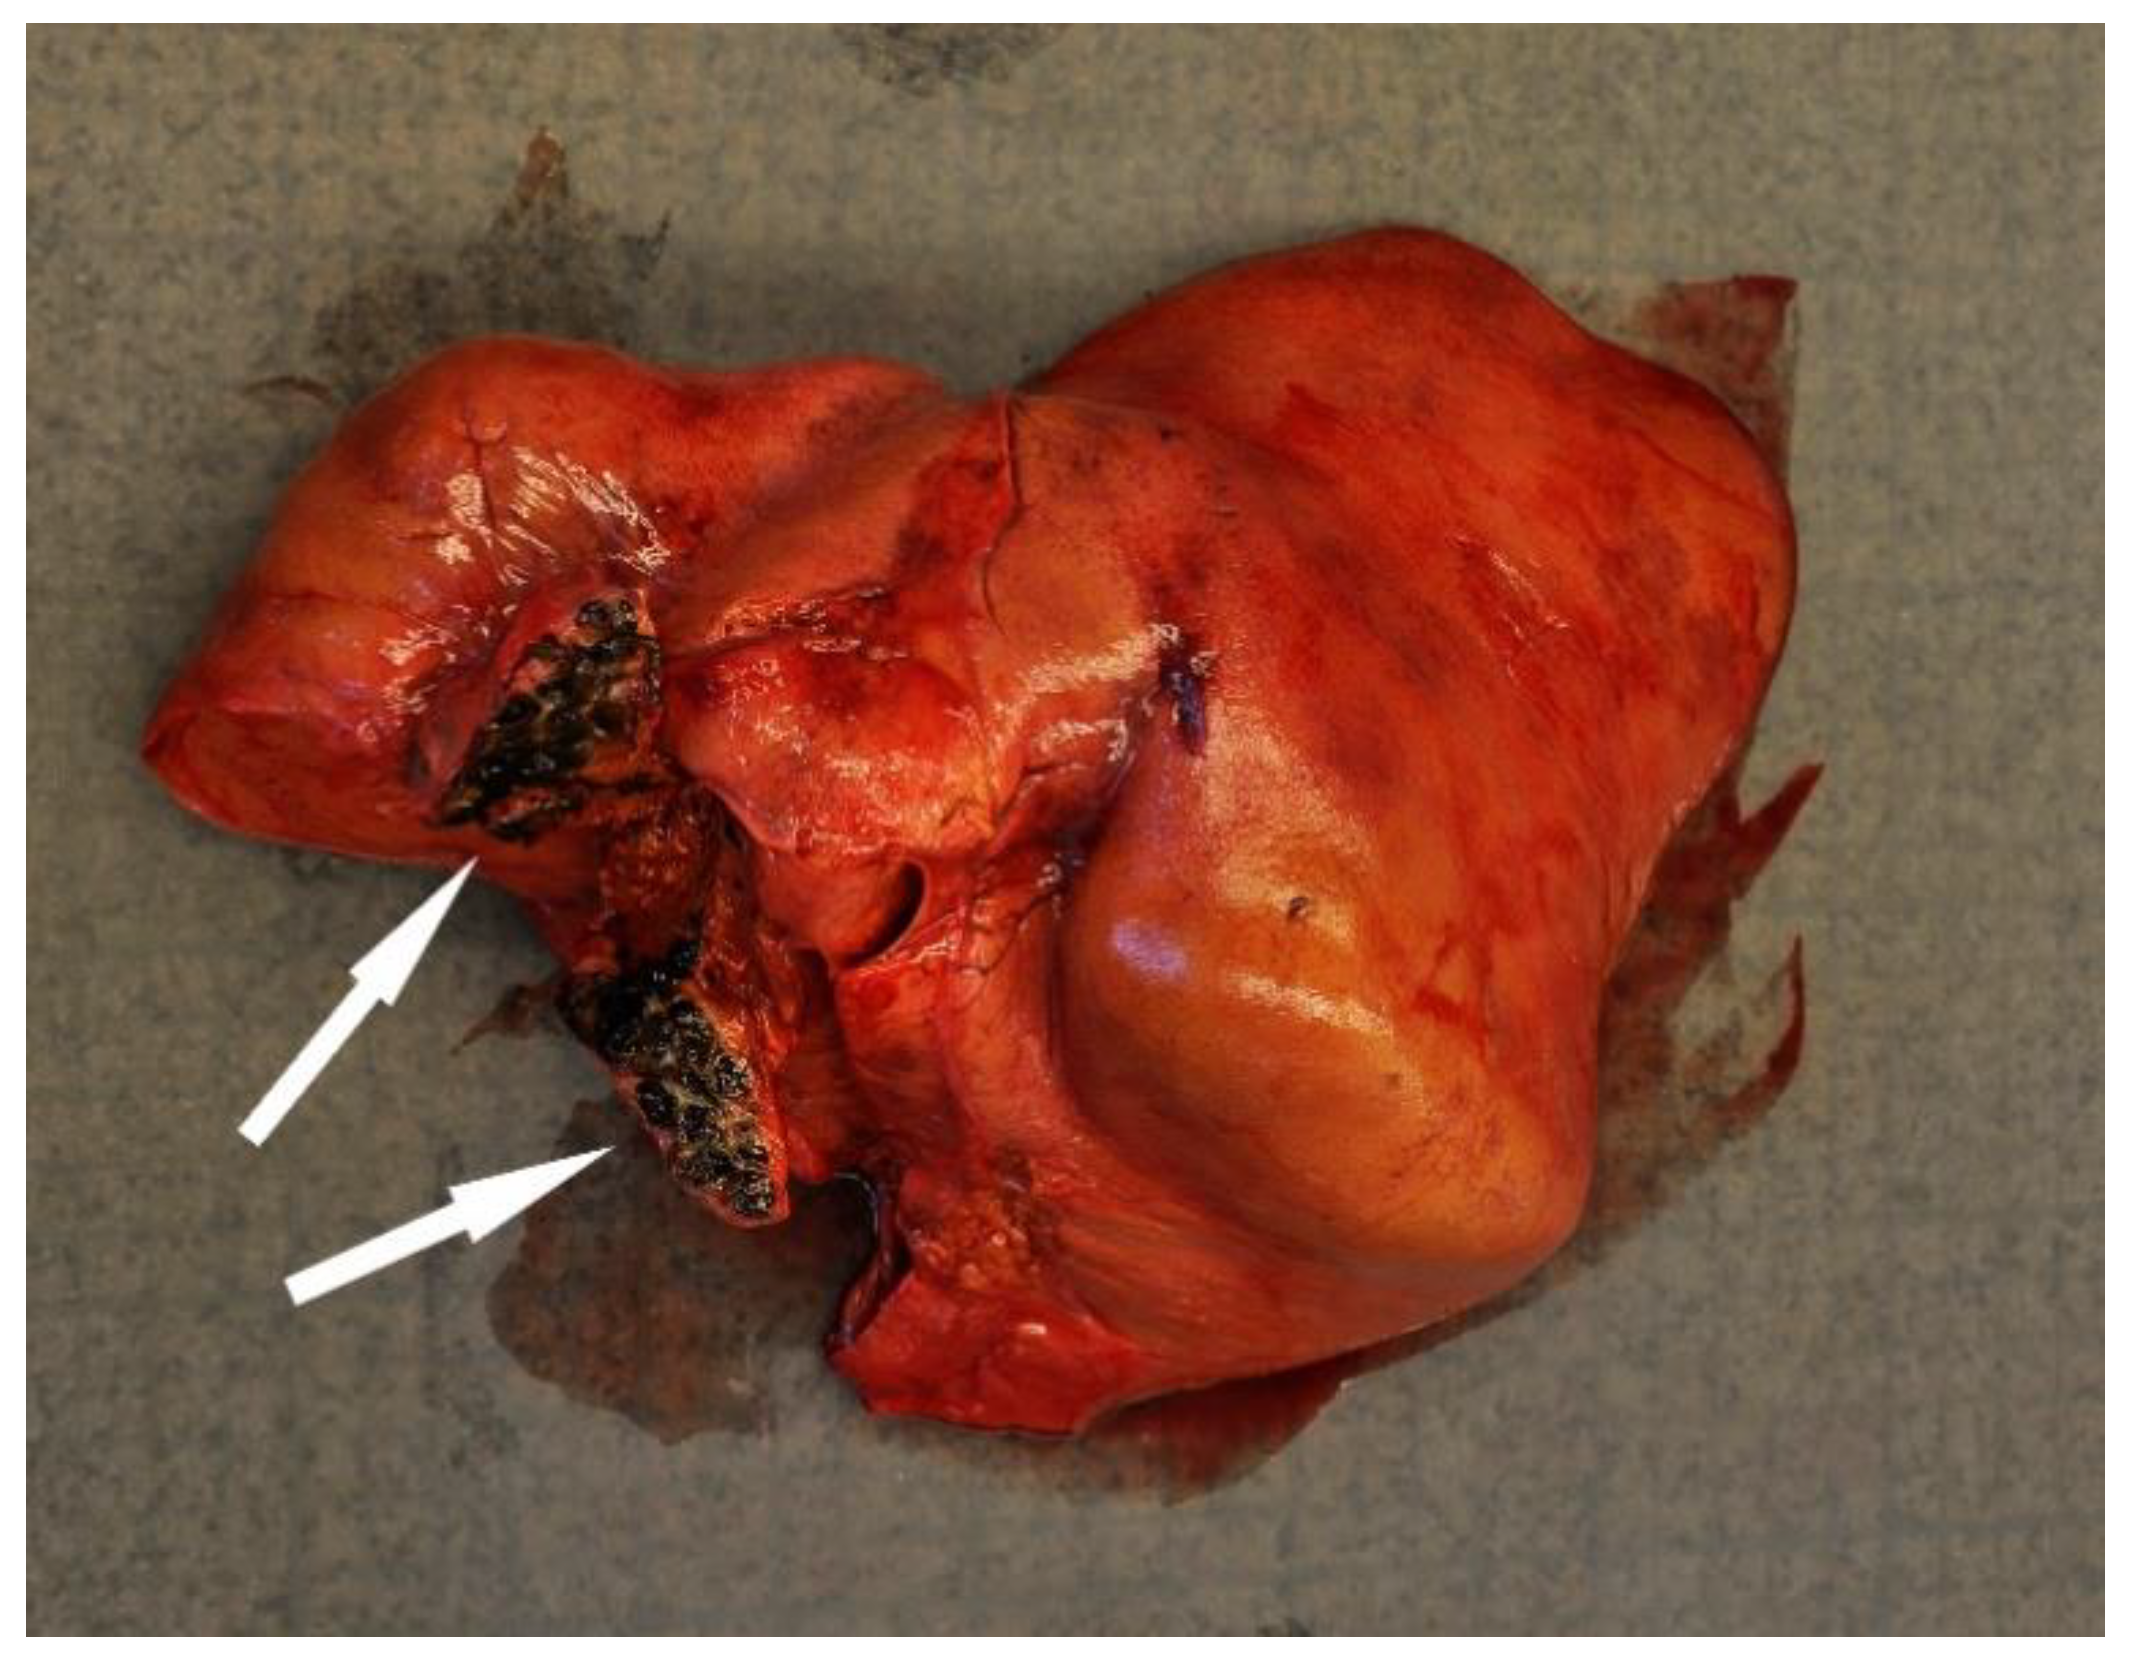

Disease was the second-most common cause of stranding or death in animals suitable for examination and of these 23 cases, infectious diseases predominated (n = 19). In this case, 13 (68.4%) of the 19 porpoises that succumbed to infectious disease were in poor to emaciated nutritional condition. Infectious diseases were caused by bacterial infections (n = 10), parasitic infections (n = 6), fungal infection (n = 2) and brain inflammation (encephalitis) of undetermined cause (n = 1). Of the bacterial infections, seven manifested as pneumonia. All seven of these animals also had a moderate to severe lungworm burden and severe thrombosis was evident in one of these cases. One calf suffered from sepsis as a sequela to chronic, infected bite wounds and another had a fibronosuppurative pericaditis, myocarditist and lymphadenitis (Figure 3). In the six animals diagnosed with primary parasitic infections, severe parasitic pneumonia was seen in five animals, including one animal with a large clot that obstructed airways. The sixth parasitic infection was a locally extensive, severe trematode infection morphologically consistent with Campula oblonga in the liver, which caused biliary obstruction, leading to liver failure and icterus (Figure 4). The fungal infections were pneumonia caused by Aspergillus fumigatus. Tissues from the porpoise with encephalitis were analysed for morbillivirus, but tissues were too autolysed and results were inconclusive. In total, pneumonia of various causes made up 14 of the 19 cases of infectious diseases. With respect to non-infectious disease, three of the four cases were related to parturition (one case of dystocia and two cases of stillbirth). In the fourth case, the animal suffered from severe ulcerative esophagitis and gastritis, but the underlying cause was not determined.

Figure 4.

The liver from a harbour porpoise (Phoceona phocoena) with a locally extensive biliary trematode infection (black discoloured area shown by arrows) that obstructed bile flow. The liver is discoloured bronze-yellow and the animal had generalized icterus.